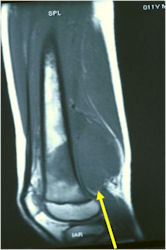

- Long Bones – Most common

- Femur: Single most common site

- Most commonly arises from diaphysis but can also arise from metadiaphysis and metaphysis;

Radiographic Presentation

- Permeative or moth eaten bone destruction

- Soft Tissue Mass in 90% of of cases